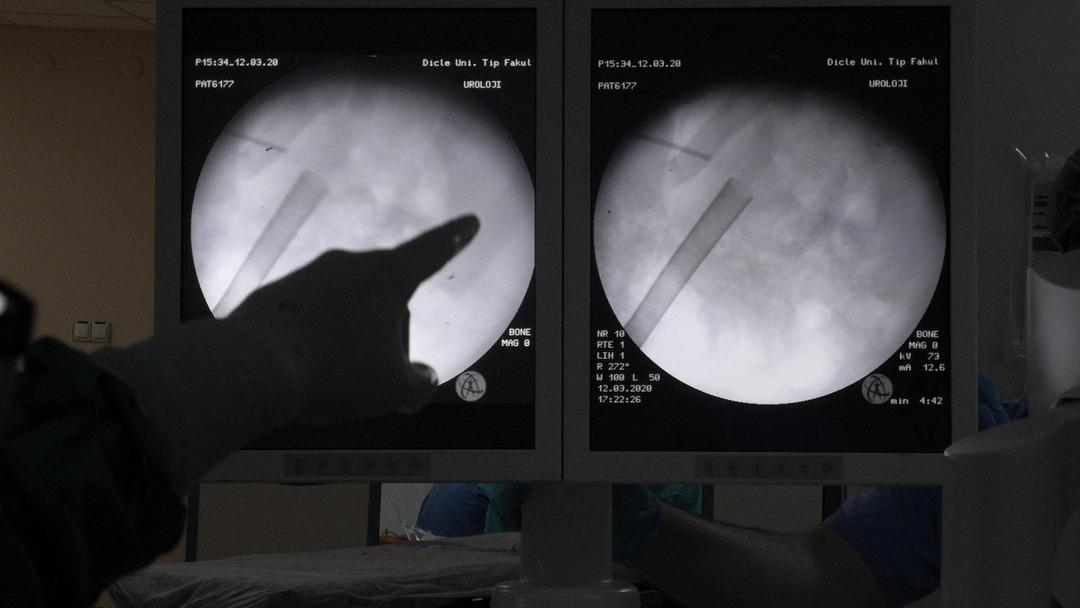

Hastaya tek delikten yaklaşık bir santim tüp aracılığı ile sırttan bir noktadan girdiklerini aktaran Doç. Dr. Dağgülli, şunları söyledi:

"Hastanın taşlarını küçük küçük parçalar halinde kırarak dışarı aldık. Yaptığımız ameliyat 2 saatte tamamlandı. Hastamızın tedavisini yaptıktan sonra evine gönderdik. Hastamızda yüzlerce taş çıktı. 6 veya 7 santimetrelik bir taşın tam bir parça halinde değil de kırarak çıkardığımız için küçük küçük parçalar halinde çıkardığımızdan yüzlerce taş çıkardık. Bu taş sadece erişkin hastalarda değil, bebeklerde de görülebiliyor. Bir yaş altı çocukların eğer sık sık karın ağrısı şikayetleri var ise idrarlarında renk değişikliği gözlemleniyorsa mutlaka ebeveynlerinin doktora müracaat etmesini öneriyoruz” diye konuştu.